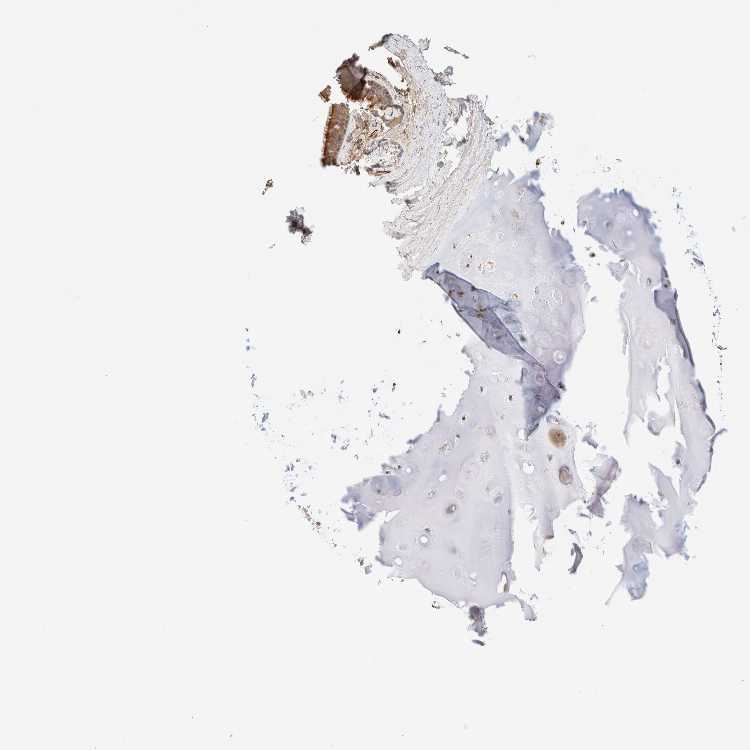

TISSUE PRIMARY DATA BRONCHUS Show tissue menu

BRONCHUS - Antibody stainingi

Antibody staining in the annotated cell types in the current human tissue is reported as not detected, low, medium, or high, based on conventional immunohistochemistry profiling in selected tissues. This score is based on the combination of the staining intensity and fraction of stained cells.

Each image is clickable and will lead to virtual microscopy that enables deeper exploration of all samples and also displays staining intensity scores, fraction scores and subcellular localization as well as patient and tissue information for each sample.

Antibody HPA001869Antibody HPA023882

Respiratory epithelial cells LowMedium